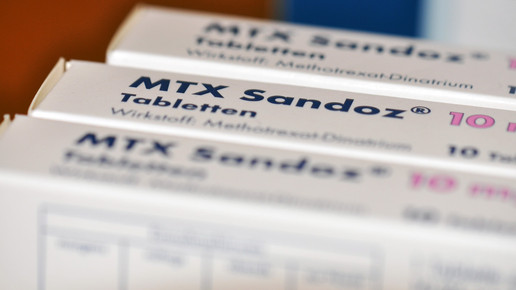

MTX – häufig nicht als Zytostatikum wahrgenommen

MTX ist ein Immunsuppressivum und Zytostatikum aus der Gruppe der Folsäureantagonisten. Der Wirkstoff hemmt vor allem die Vermehrung von sich schnell teilenden Zellen und wird unter anderem bei Multipler Sklerose, Psoriasis, Morbus Crohn und Lupus eingesetzt. Aufgrund des Wirkmechanismus kommt es zu dermalen Nebenwirkungen wie Ausschlag, Juckreiz und Trockenheit. Wichtig für die Empfehlung einer geeigneten Pflege: Die Grunderkrankung.